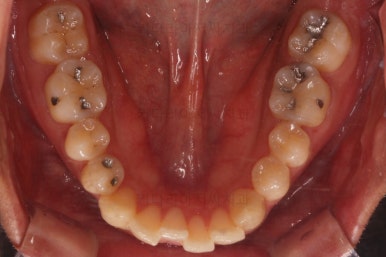

초진 시 입안의 모습입니다.

앞니가 약간 삐뚠 것 말고는 큰 문제는 없어보이네요.

교합이나 가지런한 느낌 매우 좋아졌고요.

특히 옆 라인에서도 둥글었던 윗입술도 오목한 곡선이 생기면서 돌출감이 좋아졌고 턱끝의 윤곽도 생기면서 무턱 느낌도 좋아졌습니다.

윗니의 위치를 보면 처음은 아랫입술에 가려질 정도로 아래로 내려와 있었는데 치료 후에는 앞니가 보이는 정도로 위치 조절이 잘 되었네요.